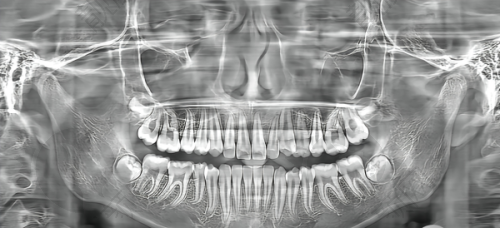

湘潭市中 心医院口腔科是一个集临床、教学、科研为一体的综合性口腔临床医学基地。在湘潭市属综合医院口腔专科中,它规模较大,具有较强的综合实力。科室拥有专精技术人员7人,配备了5套精良的牙科综合椅、Root根管长度测量仪、意大利啄木鸟洁牙机、光固化机、德国牙科X片机、全景X片机、高频铸造系统等精良设备。